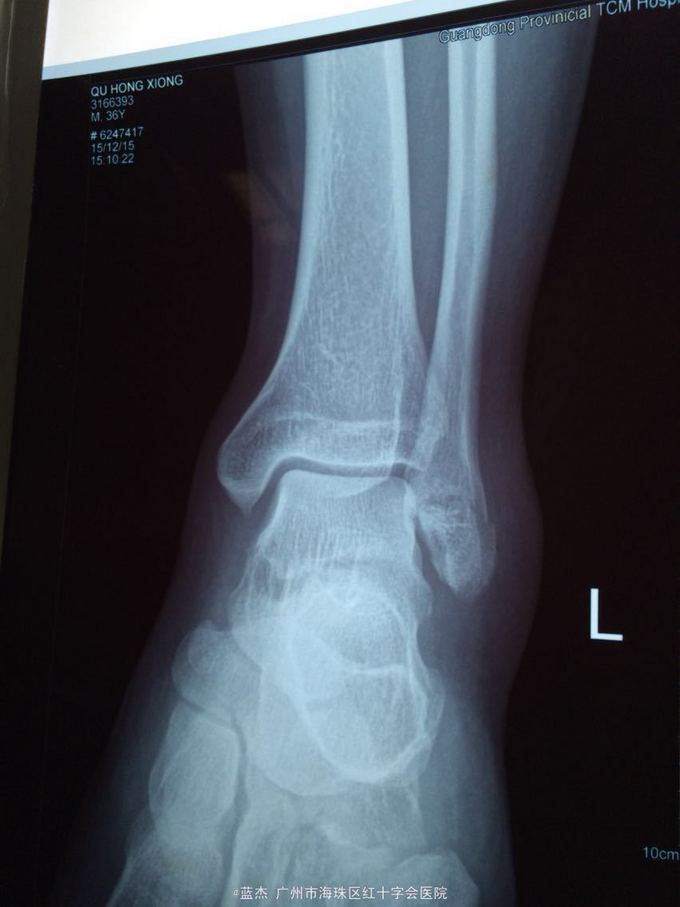

主诉:左踝关节疼痛肿胀伴有活动受限6小时。 病史:患者6小时前打篮球时不慎扭伤左踝关节,致使左踝关节疼痛,肿胀,伴有活动受限。遂到xx骨伤科医院就诊,接诊医生建议患者手术治疗,患者本人考虑到可以保守治疗,签名拒绝手术治疗后,遂来我院治疗,现见患者左踝关节外侧疼痛,肿胀,活动受限,无其他不适。

查体:左踝外侧压痛,左踝的背伸,跖屈功能可。

诊断:腓骨骨折 处理:外敷双柏散膏+小夹板固定,口服活血止痛汤7剂。每隔2天换一次药。

随访:一月后复查X片,骨折处对位对线良好,功能活动度可,肿胀消除,可正常下地行走,少许疼痛。行去除小夹板,继续外敷药+骨科外洗药治疗,7周后行走正常,疼痛基本消失。 讨论:请问各位医生,这种情况在大医院或者专科医院是不是一定要手术治疗?有些时候保守治疗的效果也是不错的。